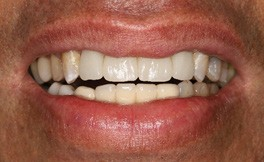

After 3 months of tissue training, patient returned for his final evaluation prior to final restoration.

Pt was ready to proceed with the final restorations and was referred back to his restoring doctor for his final bridge.